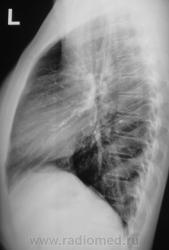

Контроль после флюорографии или "Красавица цыганка".

Парамеастинально в С-1 справа инфильтрат.

Левая верхушка не отпускает.sad

Похоже на фокусы S1S2 с об.сторон с перифокальной инфильтрацией и без деструкии. Фтизиатр консультировал? В среднем поле справа еще один увидел.

Могу ошибаться, но я бы лично поставил норму.